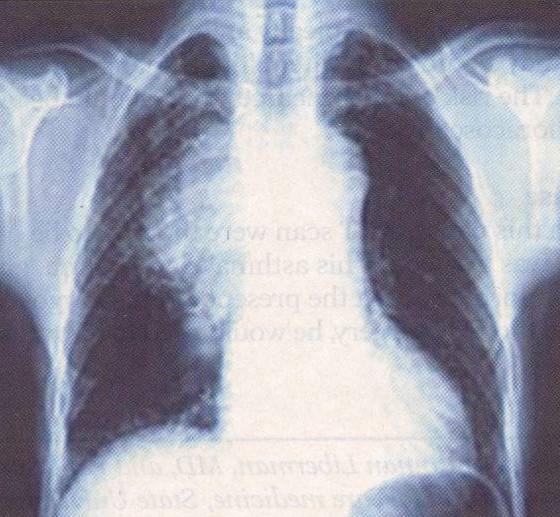

test. The strength of his proximal leg muscles was diminished (2/4). His chest x-ray

is shown below.

Chest x-ray shows a mass in the right parahilar region. Biopsy of the mass revealed squamous cell lung cancer.